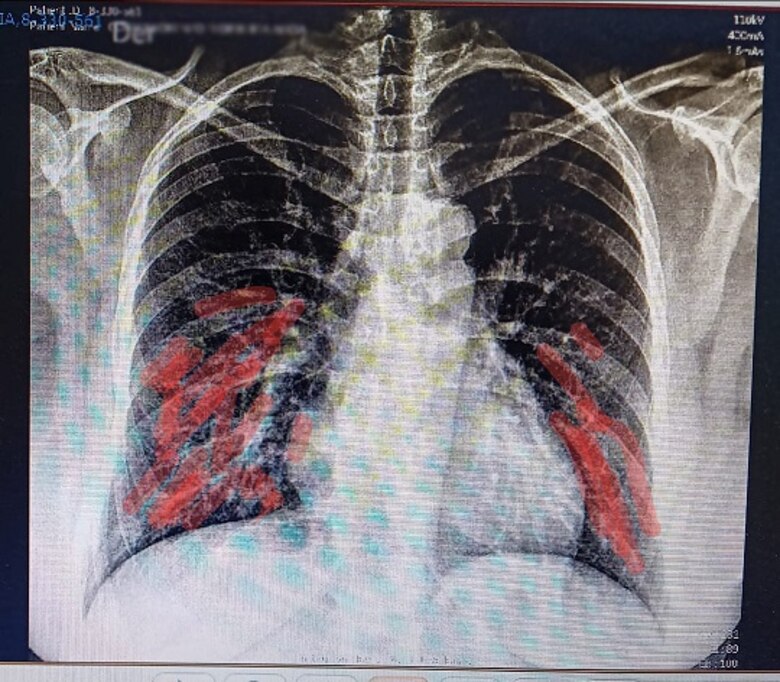

Luego de la gasometría, me hicieron exámenes de sangre y me llevaron a Radiología, para tomarme unas placas de los pulmones. Siempre con el oxígeno a mi lado.

Pasada las 11:00 a.m., conocí a quien sería mi doctor de Medicina Interna, durante mi estancia en el Modular. Su diagnóstico fue: “neumonía de leve a moderada”, que había afectado un tercio de mis pulmones. Debido a esto, aumentaron la cantidad de corticoides y harían un CAT y más radiografías.